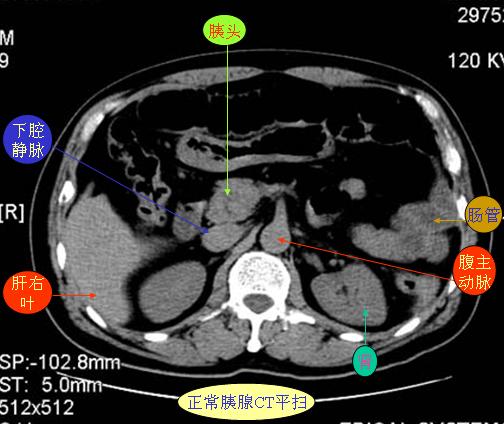

腹部ct解剖与基本病变